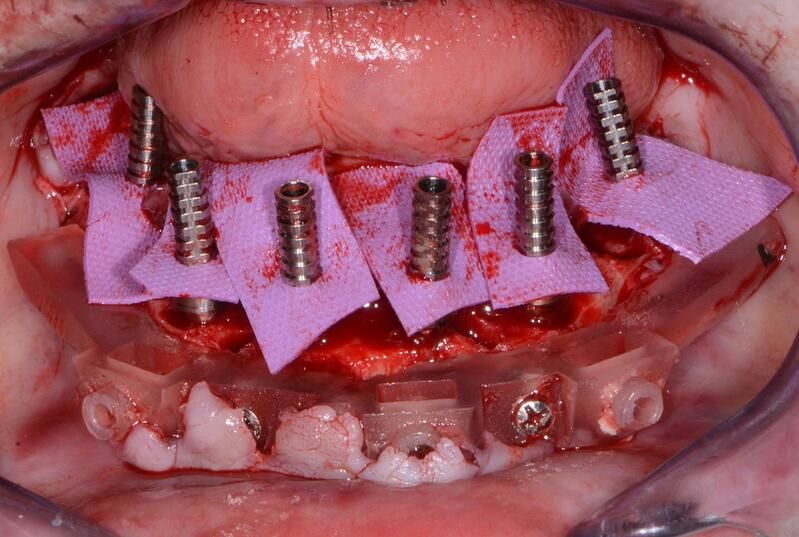

術(shù)中過(guò)程